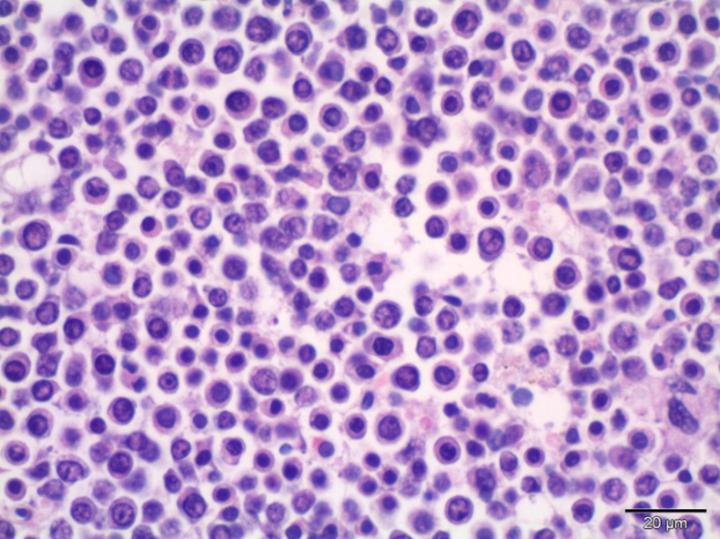

Το πολλαπλούν μυέλωμα είναι μία αιματολογική κακοήθεια που οφείλεται στον ανεξέλεγκτο πολλαπλασιασμό των πλασματοκυττάρων δηλαδή κυττάρων που παράγουν αντισώματα στον μυελό των οστών. Αποτελεί τη δεύτερη συχνότερη αιματολογική κακοήθεια. Παρά την πρόοδο που έχει επιτευχθεί, οι ασθενείς κάποια στιγμή υποτροπιάζουν ή γίνονται ανθεκτικοί στις υπάρχουσες θεραπείες. Τον Νοέμβριο 2015, ο αμερικανικός οργανισμός τροφίμων και φαρμάκων ενέκρινε τη δαρατουμουμάβη (μονοκλωνικό αντίσωμα) ως μονοθεραπεία στην αντιμετώπιση ασθενών με ανθεκτικό ή υποτροπιάζον μυέλωμα. Η δαρατουμουμάβη επάγει τον κυτταρικό θάνατο μέσω μοριακών και άνοσων μηχανισμών και βοηθά συγκεκριμένα κύτταρα του ανοσοποιητικού συστήματος να επιτεθούν στον όγκο.

– Αναρρόφηση μυελού των οστών ή βιοψία για τον προσδιορισμό του ποσοστού των μυελωματικών κυττάρων στον μυελό, καθώς και άλλων γενετικών ανωμαλιών.